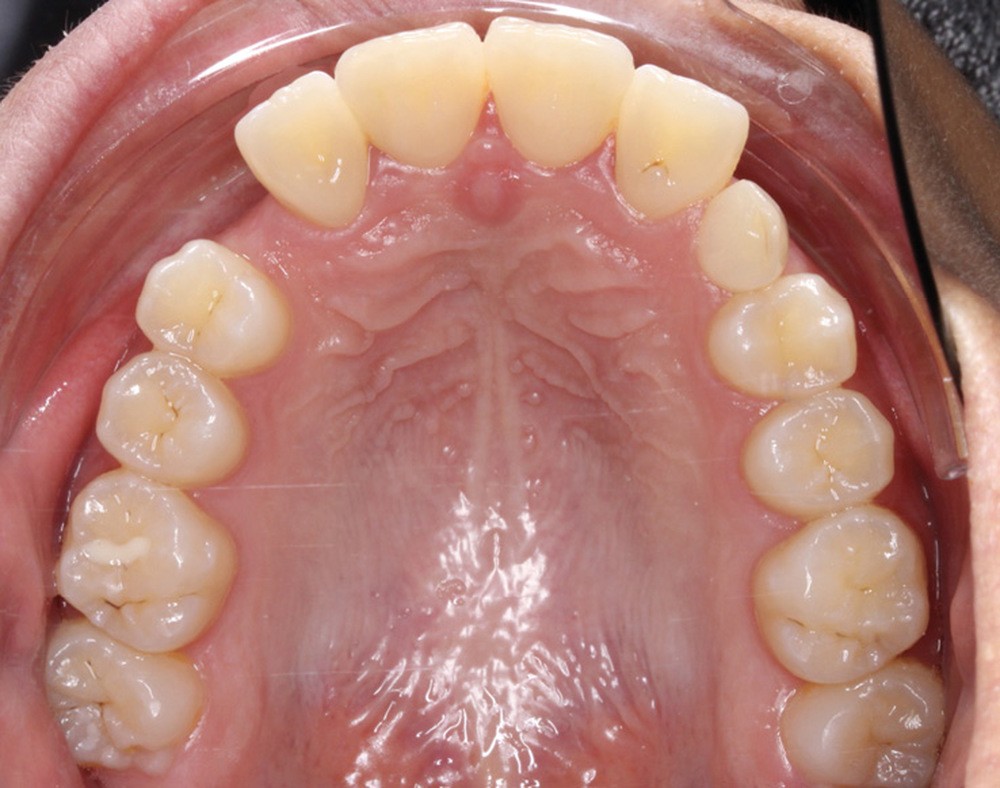

Les examens cliniques et radiologiques ont mis en évidence l’inclusion de 13 et 23, une légère classe II bilatérale par perte d’ancrage, un biotype parodontal de type IV de Maynard et Wilson avec une insertion du frein mandibulaire antérieur papillaire, une biproalvéolie et une typologie hypodivergente. La réalisation d’un examen tridimensionnel a permis de confirmer la localisation palatine de 23 et vestibulaire de 13 ainsi que de visualiser l’étendue des résorptions radiculaires touchant 12, 21 et 22 (fig. 1a-i).